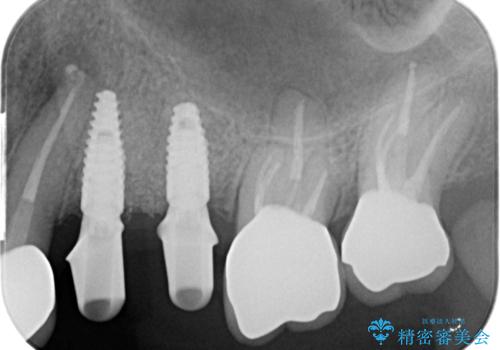

銀歯を除去したのち、虫歯を丁寧に除去し、歯を残せるのかどうかをしっかりと評価し、長期的な予後を見据えた虫歯治療を行っていきます。

- 154万円(インプラント×2・チタンカスタムアバットメント×2・ジルコニアクラウン×6・仮歯×6)費用は治療当時の料金となります

銀歯の下で虫歯が再発していた歯は、無理に残しても割れてしまう可能性が非常に高いと考えたため、相談の上抜去を行いインプラント治療を行っていくこととしました。